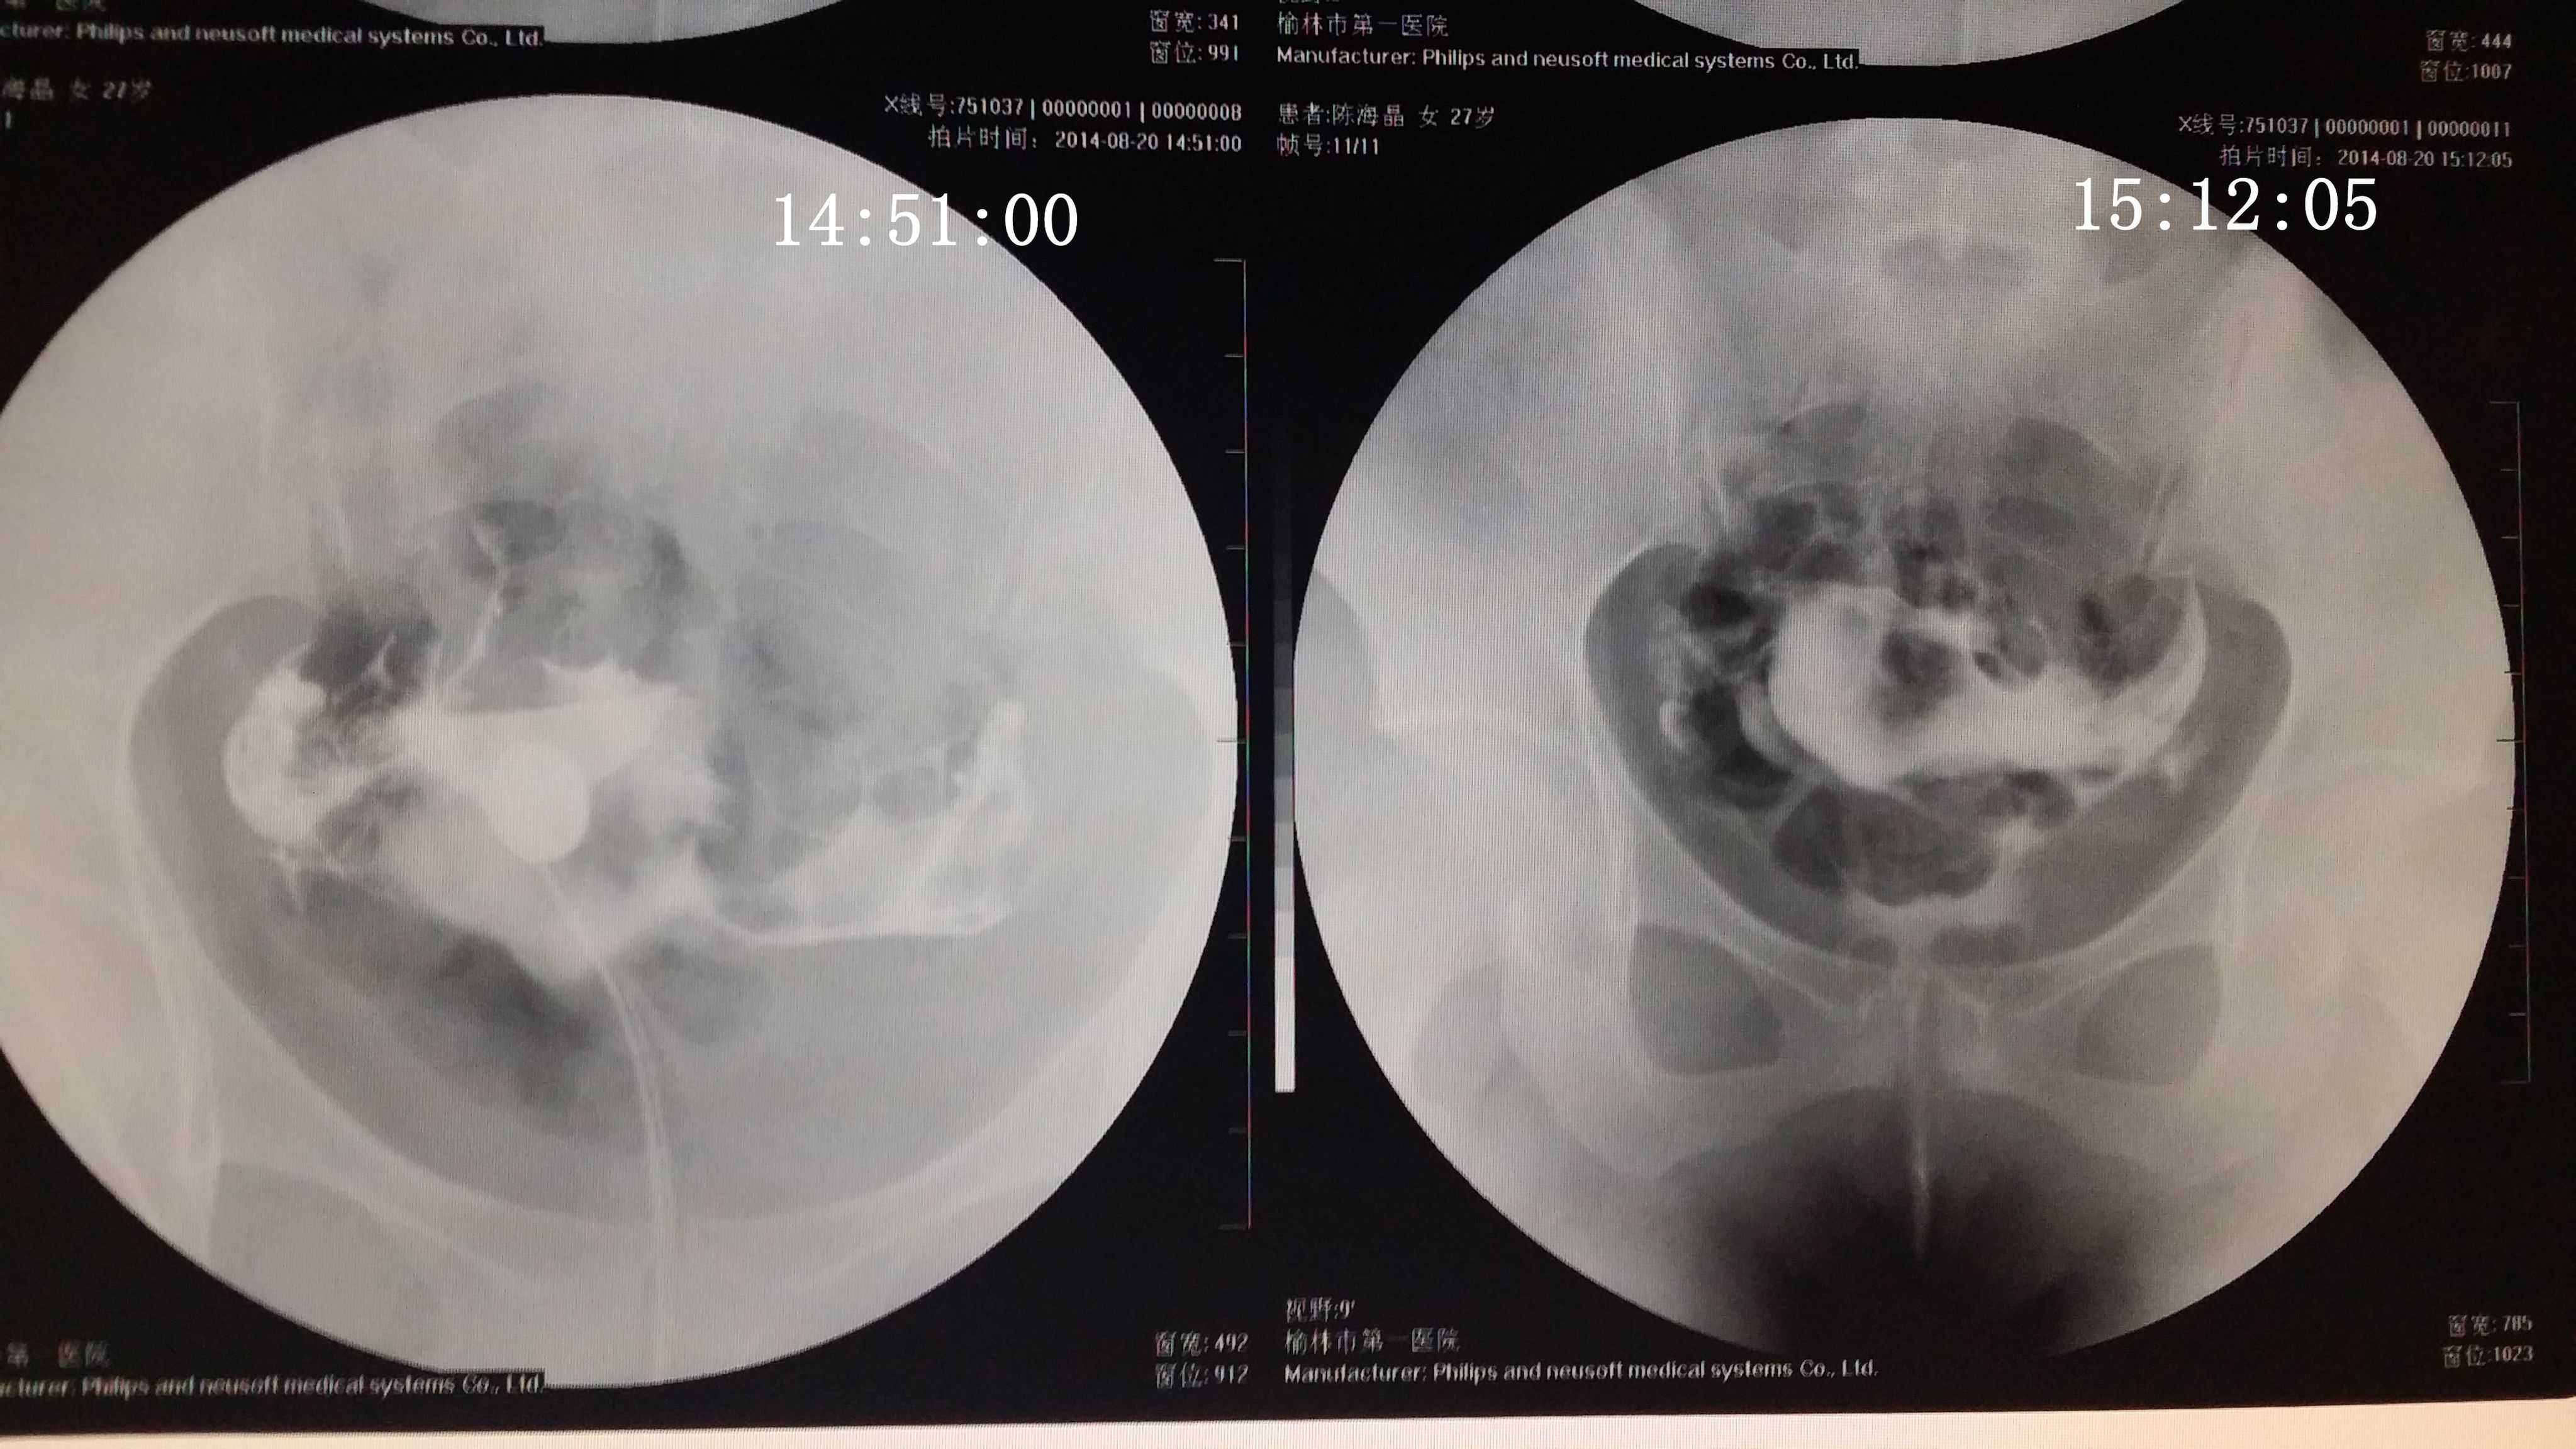

请专家帮我分析下我的造影片 医生诊断说是没问题,只是右侧输卵管伞部有点弯曲不直,说左侧通着可 以自然受孕,不知道会不会有错,之前在其他医院没做造影直接做的通液,说是阻力很大,堵的厉害后过几个月在另一家医院做的这个造影片。(另之前有过盆腔积液,但已经治疗好了} 造影都好几天了右侧一直觉得酸痛的,是不是又发炎了啊,吃药可以吗? 点击展开 匿名用户 2014-09-04 20:09 为您推荐: 其他回答 你好,这个还好的啊,这个不是已经通过了里面,这个这样就是不会有什么事情的 的哦 生活还在继续66 2014-09-05 14:56 相关问题 输卵管通而不畅,迂曲右侧上举,请问济南哪个大医院治疗这个专业啊~请有经验的人告诉下~急急急另附造影片 输卵管伞端不通怎么办 如果排了,B超能检测出来吗?B超单上会显示什么?12月22号做的造影,结果是右侧输卵管伞端通而不

以自然受孕,不知道会不会有错,之前在其他医院没做造影直接做的通液,说是阻力很大,堵的厉害后过几个月在另一家医院做的这个造影片。(另之前有过盆腔积液,但已经治疗好了} 造影都好几天了右侧一直觉得酸痛的,是不是又发炎了啊,吃药可以吗?